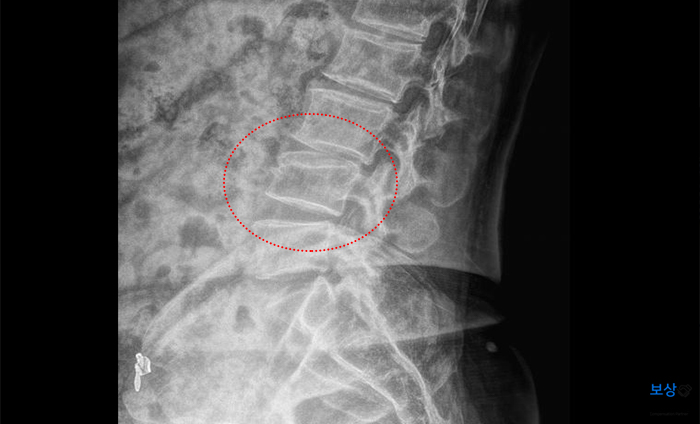

진단명 : 외상성 지주막하 출혈 (s06.60) 압박골절, 허리 (s32.090) 외측복사의 골절, 폐쇄성 (s82.60) 늑골 다발골절, 폐쇄성 (s22.490) 사고로 인한 두개골 충격으로 지주막하에 출혈이 발생하였고, 허리뼈 L4 (요추 4번) 압박골절, 그리고 발목 복사뼈 골절과 갈비뼈 골절까지 입으셨는데요. 충격이 얼마나 컸는지를 짐작해볼 수 있습니다.

이 중에서 특히 허리 L4 (요추4번) 척추 압박골절 증상을 유의해야 하는데요. 별다른 수술적 치료 없이도 후유장해 요건에 해당되기 때문입니다. 회복 후에 통증이나 후유증이 남지 않았다고 해도 찌그러진 척추체는 영구적으로 복구가 되지 않는데요. 그러므로 요추 또는 흉추 골절은 후유장해 보상금을 신청할 수가 있습니다.

맥브라이드 장해 평가를 통해 노동능력 상실률을 계산하여 청구가 진행되었는데요. (L4, 요추 4번 압박골절)